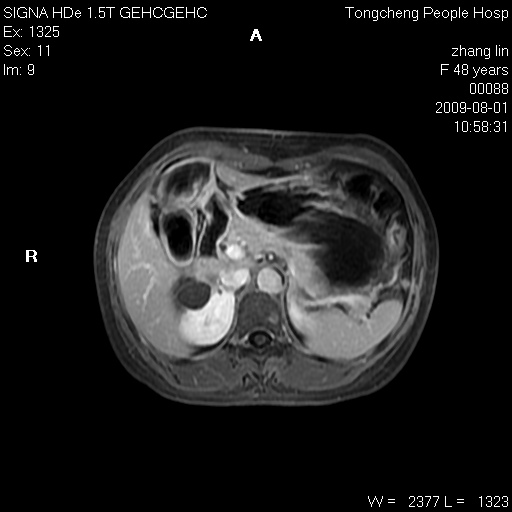

女,48岁。健康体检,彩超发现右肾占位性病变。平素健康。

临床诊断:右肾占位性病变,性质待定(囊肿?肿瘤?)。

上中腹部mr平扫+增强扫描,图像如下:

右肾上极见一类圆形病灶,t1wi呈等信号t2wi呈等高混杂信号,三期增强无强化,边界清---考虑囊肿出血。

同反相位均表现为等信号,病变无强化,考虑含蛋白的囊肿可能,弥散加权相或许有些帮助,